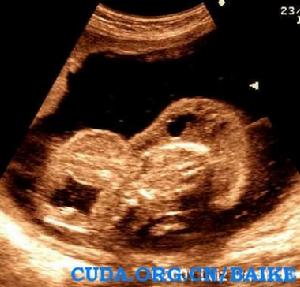

超聲特徵:

· 特徵性表現是都卜勒出現反向動脈灌注。可見臍動脈血流從胎盤朝向無心胎,靜脈血流則反向。這是由於無心胎沒有心臟泵血只能依靠與胎盤的動脈-動脈交通從正常胎兒處竊血。

· 異常胎兒頭極,心臟,上肢及許多內臟受損。下肢相對保持但是足內翻和腳趾異常普遍可見。

· 兩血管臍帶。50%單臍動脈。

超聲圖例: